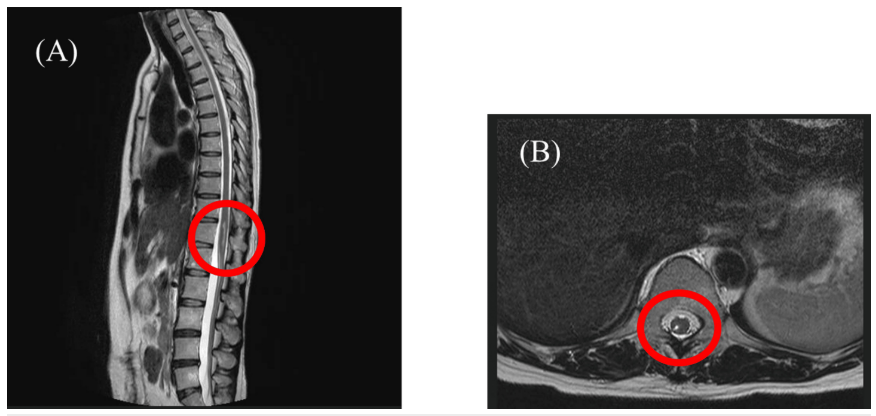

患者為49歲女性(身高151cm,體重53kg,BMI 23.24),主訴右下肢疼痛伴麻木。2021年12月因結(jié)腸癌行腹腔鏡結(jié)腸切除術(shù)時(shí)接受硬膜外麻醉,術(shù)中出現(xiàn)右下肢電擊樣劇痛,術(shù)中至術(shù)后留置導(dǎo)管進(jìn)行鎮(zhèn)痛。硬膜外導(dǎo)管拔除后,右下肢持續(xù)存在疼痛及麻木癥狀。T2加權(quán)磁共振成像(MRI)通過高信號(hào)顯像反映組織損傷及水腫導(dǎo)致的水含量增加,本病例顯示胸腰段脊髓損傷伴第12胸髓區(qū)域積液。因治療后癥狀持續(xù)存在,患者于2022年5月轉(zhuǎn)至疼痛科就診。既往史除結(jié)直腸癌及卵巢囊腫治療史外無特殊。初診時(shí)患者自訴右大腿至膝關(guān)節(jié)疼痛,靜息狀態(tài)下數(shù)字評(píng)定量表(Numeric Rating Scale, NRS)評(píng)分為7/10,發(fā)作時(shí)達(dá)10/10。步態(tài)跛行,行走時(shí)疼痛最為劇烈。查體發(fā)現(xiàn)右下肢肌力減退,踝關(guān)節(jié)背屈偶發(fā)困難。胸腰椎MRI顯示T11-T12脊髓水平(右后角至后索)水腫,未見其他脊髓病變或畸形。

脊髓于T11-T12胸椎水平(右后角至后索)呈現(xiàn)水腫影像,未檢出其他腰椎病變。(A)矢狀面觀;(B)橫斷面觀